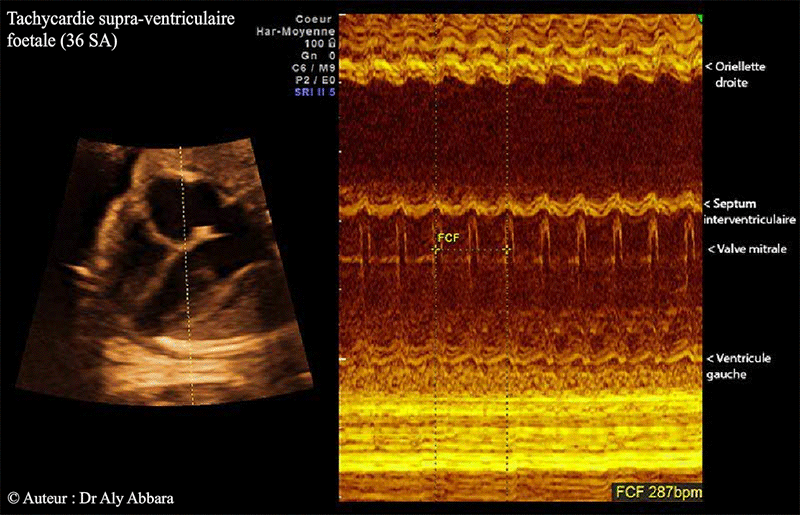

Tachycardie supra ventriculaire à 36 SA - Mode TM - Doppler

• Chez un fœtus de 36 SA : images échographiques en temps réel montrant une tachycardie supraventriculaire à 287 battements par minute avec une fréquence auriculaire et ventriculaire identiques (ratio A:V = 1:1 sur l'analyse en mode TM).

• On observe sur ces images un myocarde supertachycarde avec une faible amplitude de la contracture auriculaire et ventriculaire aboutissant à une nette diminution du volume sanguin éjecté à chaque cycle cardiaque. La conséquence est une insuffisance cardiaque par diminution globale de son débit globale ; elle se manifestant chez ce fœtus par une augmentation du volume cardiaque (cardiopathie dilatée) ; un épanchement péricardique modérée ; une hépatomégalie et une ascite.

• Le rapport "fréquence auriculaire/fréquence ventriculaire" ou A:V = 1:1, donc pas de bloc auriculo-ventriculaire.